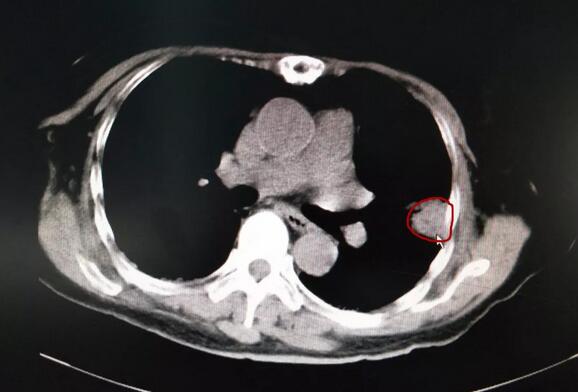

В апреле этого года тётя Ли сделала повторное обследование, которое показало, что у нее увеливение узлов в левом легким. В июле повторное КТ-обследование груди показано, что интерстициальный фиброз двух легких с инфекцией без заметных изменений с предудущим; масса в верхней доле левого легкого с увеличенным очагов; в соответствии с чрескожной биопсией аденокарцинома легкого; по EGFR экзонная мутация, PD-L1 (-), поставлен диагноз аденокарциномы верхнего левого легкого T2aN0M0 ⅠB стадии.

Затем тетя Ли госпитализирована в Онкологической больнице Фуда при Университете Цзинань, и сразу же после консультации с доктором Ню ей создали план лечения, 12 сентября медицинская команда выполнила правильные и эффективные процедуры с большим опытом и превосходными методами криотерапии, операция прошла очень успешно, интраоперационное кровотечение было всего 0,5 мл, жизненные признаки были стабильны.